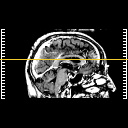

Click on sagittal image to select slice. Click on thin tickmark to change timepoint, or thick tickmark for overlay.